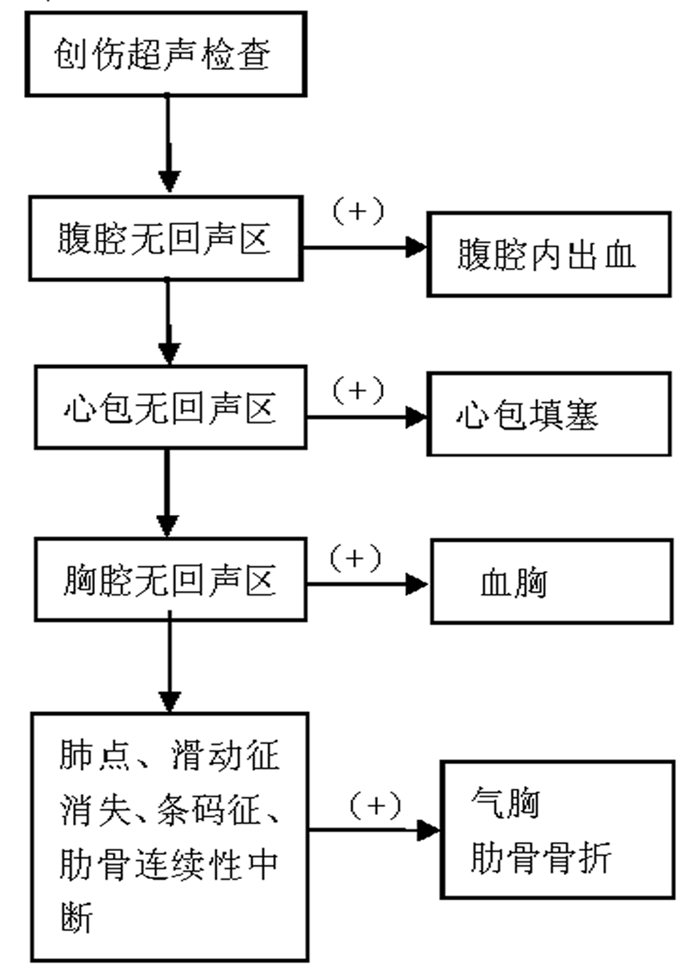

(2)创伤的超声诊断流程见图 29。

| 图 29 创伤超声诊断流程 |

3 超声的临床应用 3.1 床旁超声在创伤中的临床应用 3.1.1 概述外伤患者病情危重且复杂,部分患者外伤后昏迷或被动体位,不能有效配合检查,而各种危重外伤患者的救治都有一个“黄金时段”,因此需要找到一种快速、科学的检查方法,从而最大限度地降低外伤患者的病死率。20世纪80年代末,国外提出针对创伤的超声快速评估法,即FAST(focused assessment with sonography for trauma)[4, 5]技术,目前已成为急重症医师快速床旁评估急性胸腹部闭合性损伤患者病情最重要的工具。传统FAST检查主要利用超声快速判断腹腔有无游离积液,扩展的FAST检查(EFAST)内容扩展到包括胸腔、心包检测[6, 7]。FAST通过对胸腔、心包、腹腔以及骨盆等部位检查,判断是否存在积液(图 21)。FAST可识别由于脏器损伤而溢出的游离液体及气体,而游离液体/气体往往是器官损伤的标志。

(1)胸腹腔出血:可表现为胸腔、心包、肝周切面、脾肾间隙、耻骨上/盆腔切面存在无回声区,提示胸腹腔出血可能。

(2)心脏压塞:可表现为心外膜和心包壁层间无回声区,舒张期的右心室或右心房有塌陷。其他的征象还包括心脏摆动,心脏逆时针转位运动类似于舞蹈样动作。心脏左侧受压也可出现左房或左室壁塌陷。另外扩张的下腔静脉进一步高度提示心脏压塞。具体图像详见2.1.心脏超声图。

(3)气胸:可表现为肺滑动征消失伴A线,其诊断气胸的敏感度、特异度分别为95%和94%。M型超声下可见条码征。肺点为局灶性气胸的特异度征象,其敏感度为79%,特异度可达100 %[8]。

3.1.3 创伤的超声诊断的步骤及流程(1)创伤的超声诊断步骤:创伤患者床旁超声检查至少5个部位:①右上腹,也叫肝周切面、莫里森窝切面或右上1/4切面。如出现无回声区提示腹腔内出血(图 22-23)。②左上腹脾肾间隙,如出现无回声区亦提示腹腔内出血(图 24-25);③耻骨上/盆腔切面,如显示膀胱后或子宫后无回声区,提示盆腔出血可能(图 26-27);④剑突下切面,常用于探查心包有无无回声区(图 28),具体心包积液征象见2.1.2 常见异常超声心动声像图。⑤肺部超声,主要用于探查有无血气胸、肋骨骨折,具体征象见2.2肺超声。